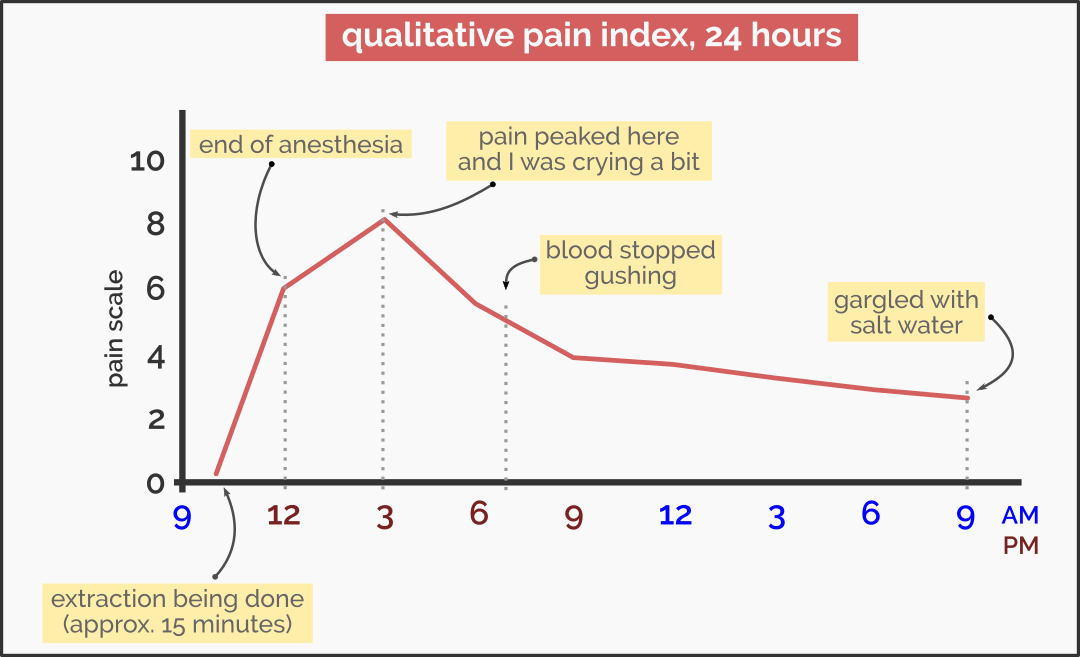

I was prescribed with three medications: mefenamic acid (painkiller and anti-inflammatory agent), antibiotics (to prevent infection), lysozyme chloride (anti-inflammatory agent), and two small bags of folded gauze pads to plug the bleeding. Anesthesia did not stay there for long. About three to four hours post-operation, the tingling feeling grew into a blunt throbbing pain intertwined with sharp pain. I think it would help if I show you my pain index 24 hours post-operation.

No the blood was not gushing but exaggerating it is the way to illustrate the horror of dealing with the blood coming out of the bleeding tooth socket. I kept on changing the folded gauze pad once in 20-40 minutes, sometimes every 90 minutes because I slept. Yes, I managed to get some sleep even though the pain was ablaze.

I browsed WebMD just to be sure I was not having post-surgery complications. It mentioned the dry socket issue, which could be debilitating and could be a precursor to a painful episode of bacterial infection. Luckily, dry socket is a quite rare phenomenon and it did not happen to me. My friends exchanged words of advice and potential hysterical fears of what could go wrong, both on an equal magnitude. I was told to gargle with salt water about 24 hours post-surgery. This should help to freshen the mouth and to speed up the recovery process.